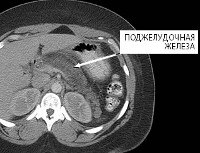

MRI of the pancreas.

МРТ поджелудочной железы. Способ сканирования органа в слоях обусловлен изменением полярности протонов атомов водорода в клетках организма под воздействием электромагнитных волн, при этом исследуемая зона находится в постоянном магнитном поле. Он используется для визуализации структуры паренхимного органа, каналов и сосудов, а также жировой ткани вокруг железы. Используется при диагностике опухолевых и кистозных образований различных типов, воспалительных и атрофических процессов, нарушений структуры. МРТ поджелудочной железы проводится в амбулаторных и стационарных условиях, обычно с контрастными веществами. Самостоятельная тренировка требуется в течение двух дней. Согласно сообщению, обследование сопровождается МРТ панкреатохолангиографии.